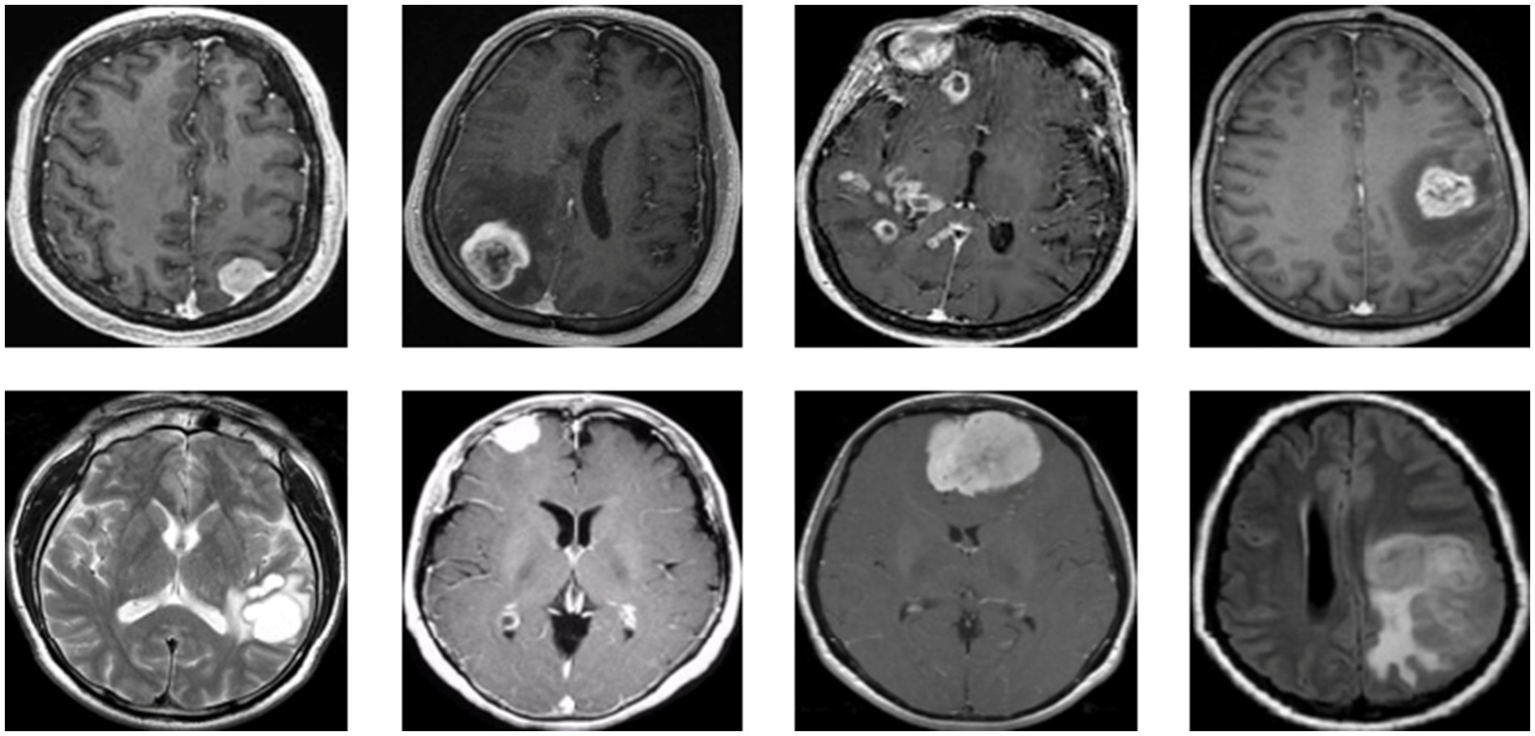

Figure 1 presents a representative MRI scan of a healthy brain, illustrating normal anatomical structures without any abnormal growths. In contrast, Figure 2 visualizes an MRI scan with a visible brain tumor, showing abnormal intensity regions that are indicative of pathological tissues. Figure 3 illustrates the distribution of MRI images across the defined classes, revealing an inherent imbalance in the dataset, which was addressed using augmentation techniques and loss function adjustments to ensure model robustness and generalizability.

Figure 2

Visualization for tumor MRI scan.

The displayed image shows a set of 10 brain scan samples, each labeled with both the ground truth (“True”) and the model’s classification result (“Pred”). In all five cases, the actual class is Brain Tumor, and the model has also correctly predicted Brain Tumor for each image. This visual representation provides qualitative evidence of the model’s effectiveness in correctly identifying brain tumor cases.

Each image appears to be a medical imaging scan—likely from MRI modalities in Figure 10—processed in grayscale. The tumors are visible as brighter or differently textured regions in the brain scans, suggesting that the model was able to detect distinguishing visual features associated with tumorous growths. The consistency in correct classification across different tumor appearances indicates that the model has likely learned to generalize the underlying patterns of tumor presence effectively.

Figure 10

Predicted result.